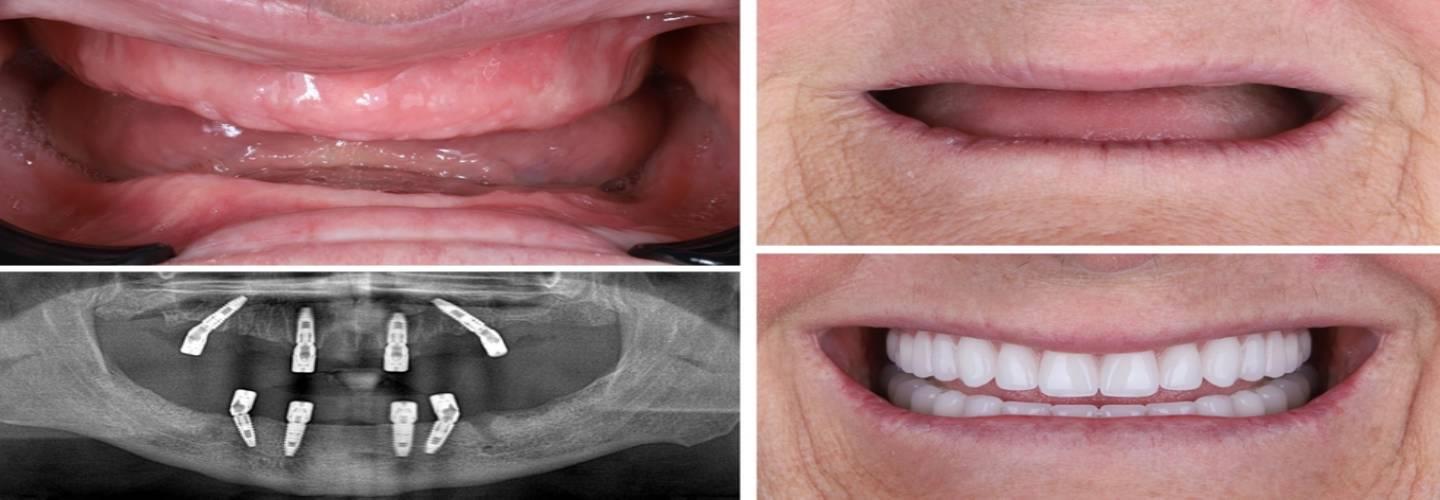

My Implant Dentist Melbourne specialises in dental implants and All-on-4 treatments for patients with missing or failing teeth. Our team delivers precise implant placement using modern imaging and guided surgery. We offer single implants, multiple implants, full-arch restorations, and All-on-4 solutions to restore chewing function and smile confidence.

Our clinic uses high-quality materials and adheres to strict safety and hygiene standards. You will receive expert care from experienced implant professionals. We aim to rebuild strong, natural-looking smiles and improve the quality of life for every patient who chooses dental implants in Melbourne.